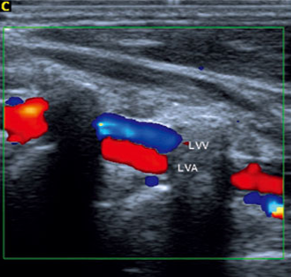

What vessel is being shown in this image?

Vertebral

Based on this image, which vessel is being shown?